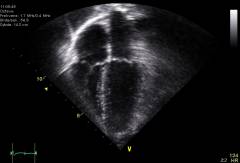

- Диагностика миокардита

Диагностика миокардита

Какие анализы выявляют миокардит?

Зачастую различные формы миокардита бывает сложно отличить друг от друга. При постановке диагноза врач должен опираться на все данные, которые он получит во время осмотра и расспроса больного, проведения обследования.